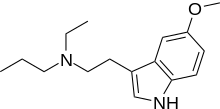

| EPT | artificial | H | CH2CH3 | CH2CH2CH3 | N-Ethyl-N-propyltryptamine | 850032-68-7 |